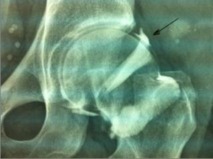

Si le diagnostic est évoqué, il faut garder à l’esprit que l’échographie met rarement en évidence une fissure du bourrelet cotyloïdien. Néanmoins, les kystes paracotyloïdiens sont des signes indirects de fissure très souvent associés à cette lésion. La reconnaissance de ces kystes est capitale pour orienter les investigations complémentaires. L’échographie permet de les identifier facilement, comme vous pouvez le voir sur la photo jointe.

Une autre difficulté est liée au diagnostic différentiel entre les kystes paracotyloïdien et les bursites du psoas dont l’apparence échographique peut être similaire. Il faut noter qu’aucune investigation ne présente une sensibilité et une spécificité suffisante pour affirmer le diagnostic de fissure paracotyloïdienne de manière définitive pour tous les cas. Actuellement, l’arthro-IRM est l’examen le plus indiqué et il est important de le proposer lorsque des images kystiques sont identifiées à l’échographie.

Conclusion: le rôle de l’échographie peut-être primordiale dans la suspicion d'une fissure du bourrelet cotyloïdien en recherchant un signe indirect lié à une complication de cette fissure, le kyste paracotyloïdien.